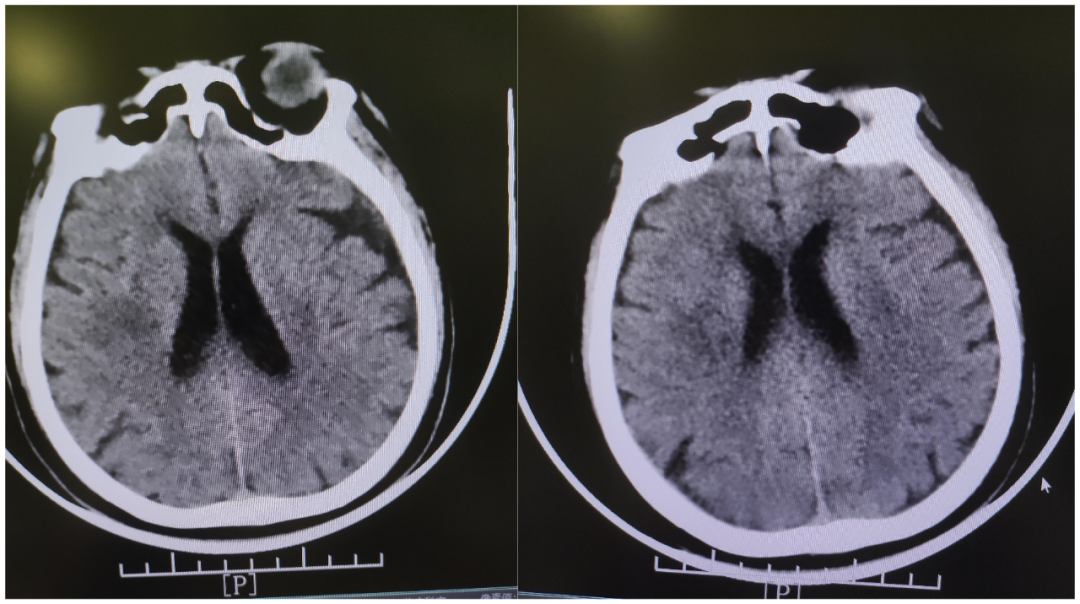

入院后,神经内科吴笃玮医师立刻对患者进行体格检查,完善头颅CT等辅助检查。患者目前处于言语欠清、口角向右歪斜,伸舌左偏,左上肢肌力0级,左下肢肌力1级状态,根据患者的检查结果,明确诊断该患者为大面积脑梗死、冠状动脉粥样硬化性心脏病等。

▲患者溶栓治疗前后CT对比

结合患者临床表现,神经内科赵庆杰教授、刘素芳主任立即带领神经内科团队启动绿色通道,急检血常规及凝血功能,患者处于溶栓时间窗内且无绝对溶栓禁忌症,符合溶栓条件。在告知患者及患者家属溶栓治疗的目的、获益性及潜在出血风险,征得家属同意并签订知情同意书后,于19:00给予阿替普酶溶栓治疗。治疗过程十分顺利,在溶栓治疗黄金时间内成功挽救患者生命。